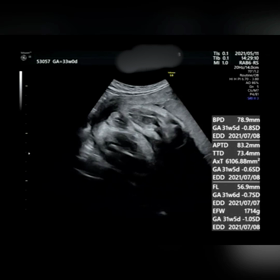

【4人目31wの健診】エコー動画と歴代4D写真

【4人目31wの健診】 エコー動画と歴代4D写真